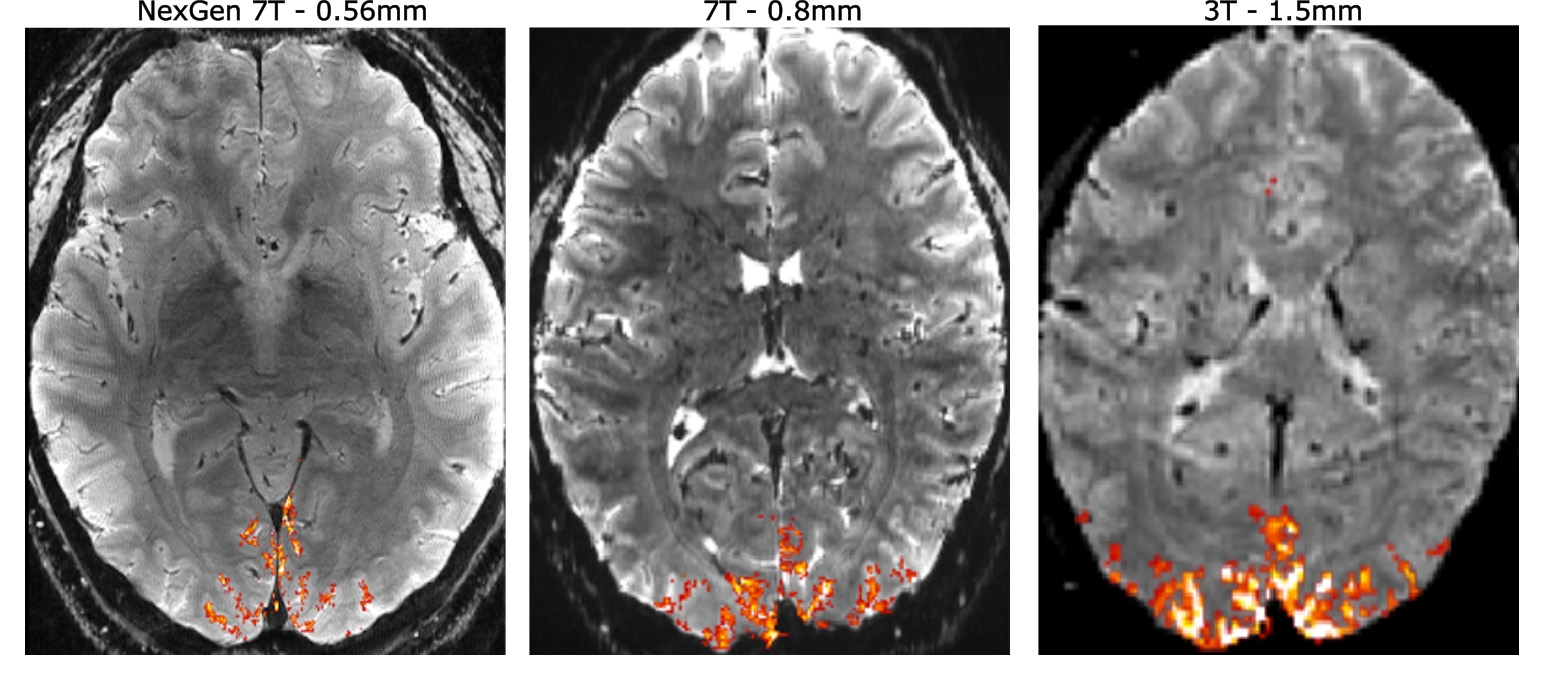

A groundbreaking study using brain scans of 140 individuals has revealed a significant surge in neural connectivity in newborns, marking a transformative stage distinct from prenatal brain growth. Conducted by researchers at New York University, the study highlights how birth triggers the formation of billions of new neural connections as the brain processes new sensory information. This growth is particularly notable in subcortical regions and parts of the frontal lobe, supporting the idea that the brain's local networks in the womb expand to global communication post-birth. The findings, published in PLOS Biology, lay the groundwork for future research on brain development during the perinatal period.